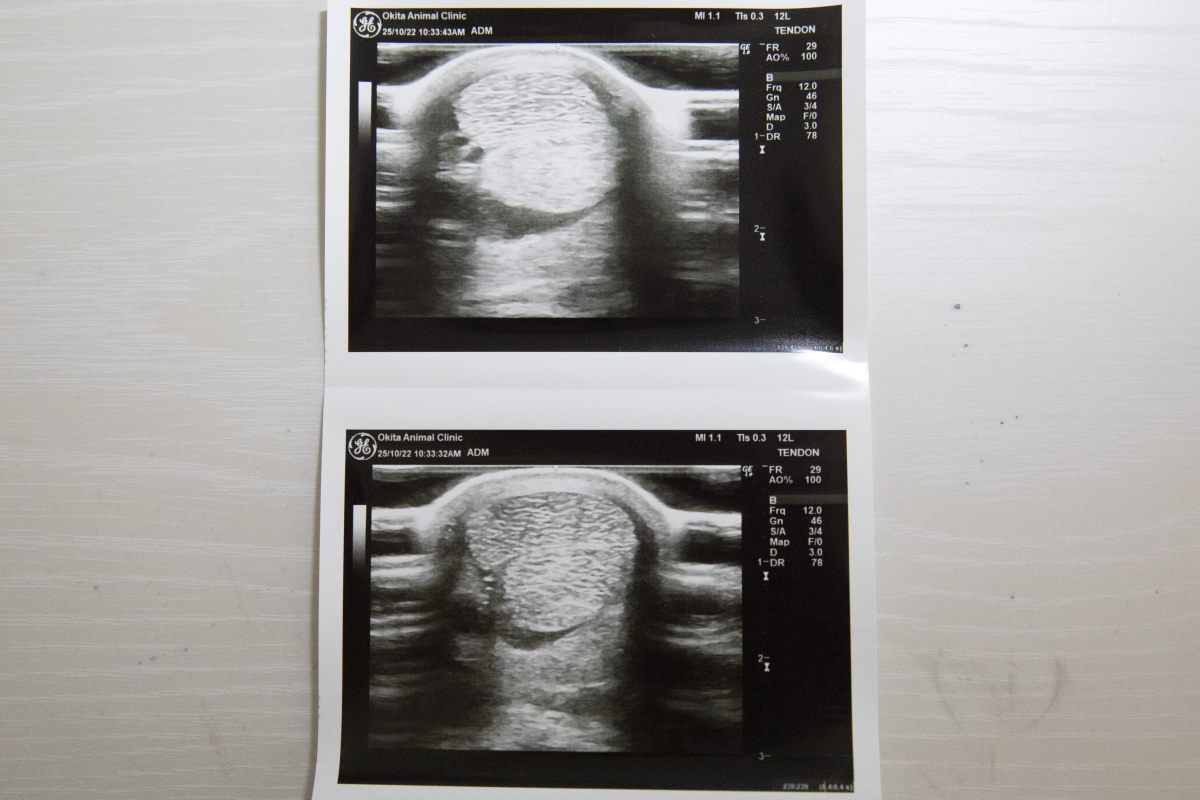

1200mではややスピード不足の印象でしたが、距離を延ばした前走は前半から行きっぷりが良すぎたほどで、かなり噛んでしまって失速したのもやむを得ません。結果的にブリンカーが効きすぎたようで、外してリズム良く折り合えれば結果は違っていたでしょう。現状は脚元にも配慮しながらの調整ですので、固まって攻め込めるようになれば変わってくるはずです。エコー検査のため、10/22に両前脚の毛を刈っています。(ホッカイドウ競馬・桧森邦夫調教師)

※右前屈腱部に慢性的な腫れが見られ、中央退厩時と前走後にエコー検査を受けましたが、腱周囲の腫れが見られたものの、腱自体の炎症は見られないとの診断でした。